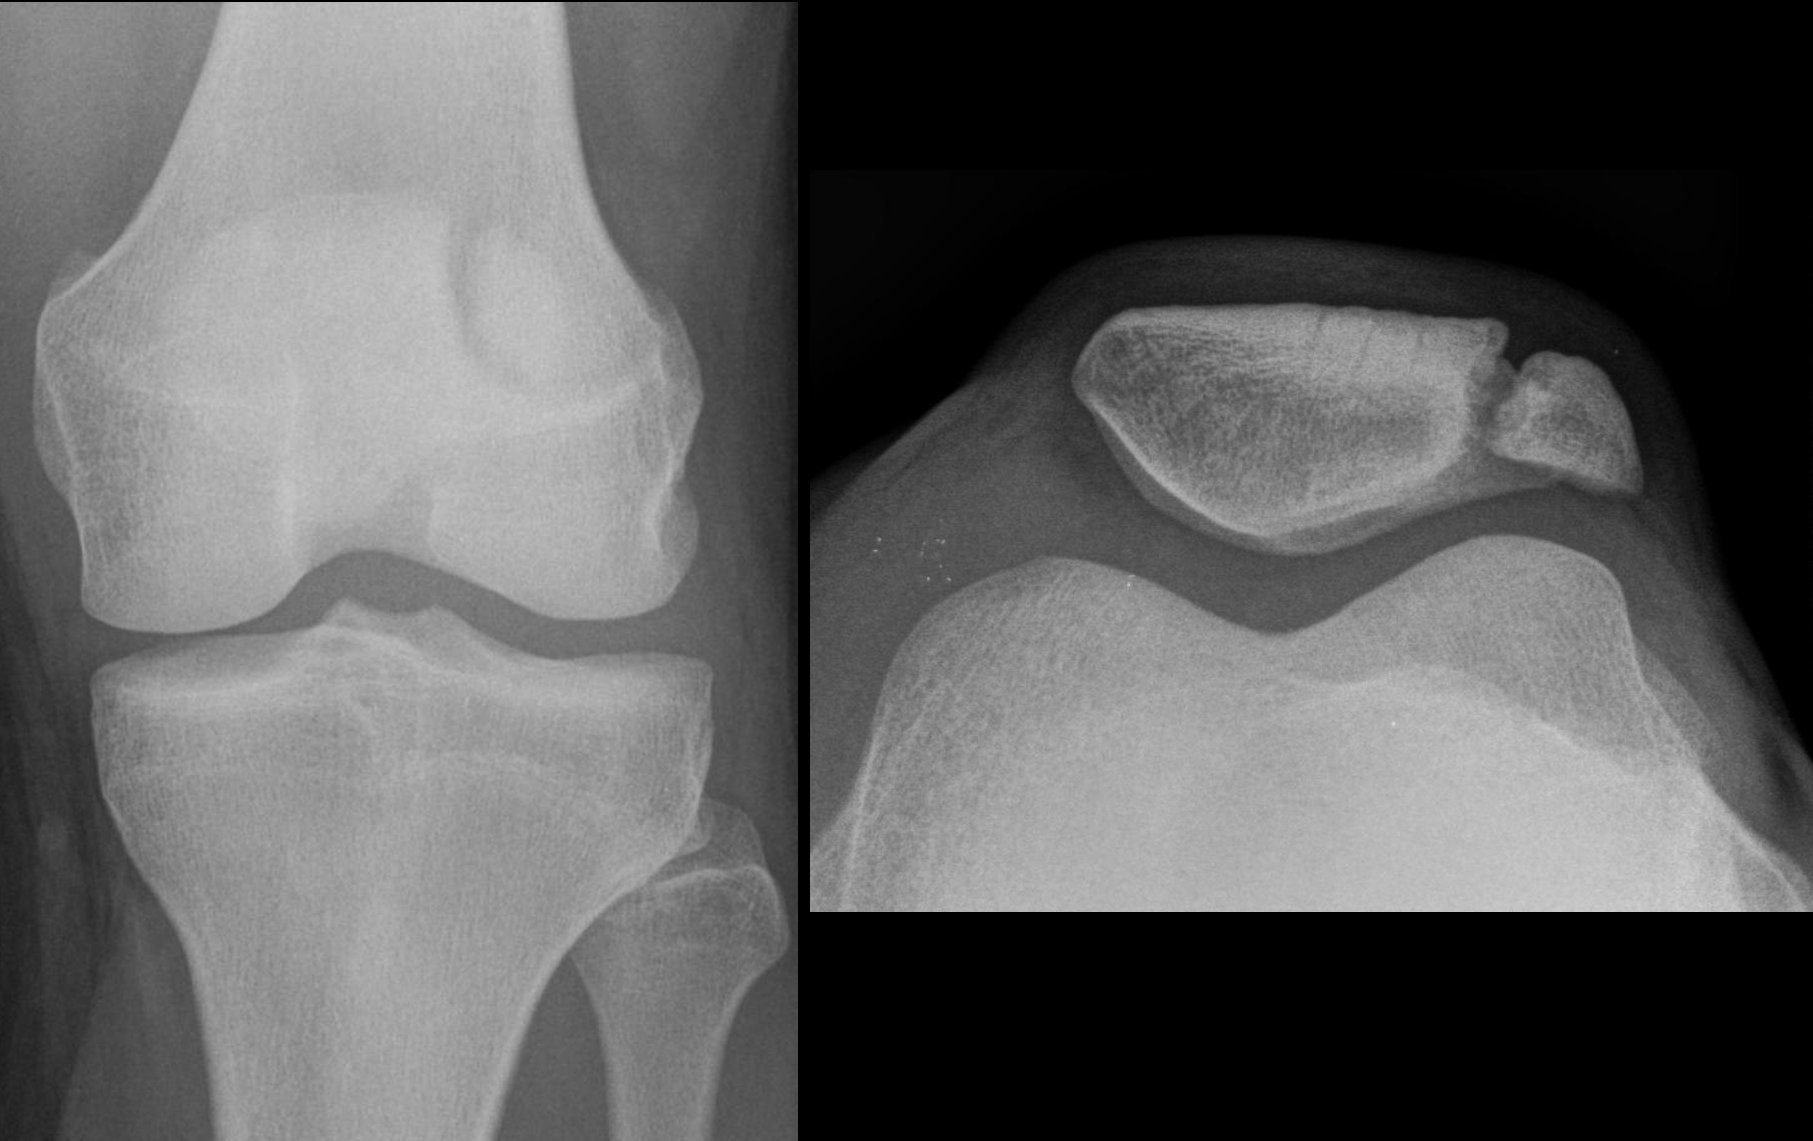

[…] had my knee appointment yesterday. The good news is that I don’t have to have my knees replaced this summer, which […]